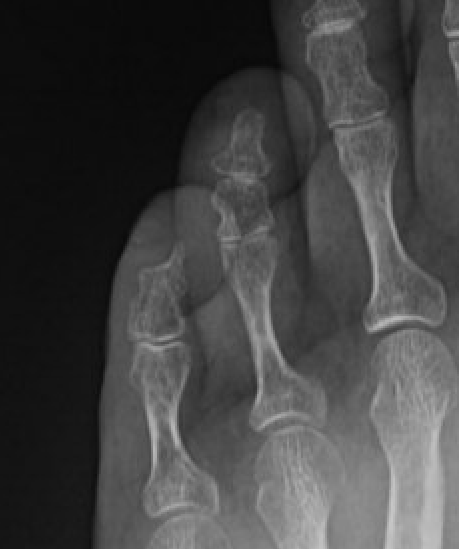

X-ray - may scallop adjacent bone on x-ray

Subungal glomus tumor distal phalanx 5th toe

MRI

Subungal glomus tumor 5th toe

Treatment - marginal excision for pain